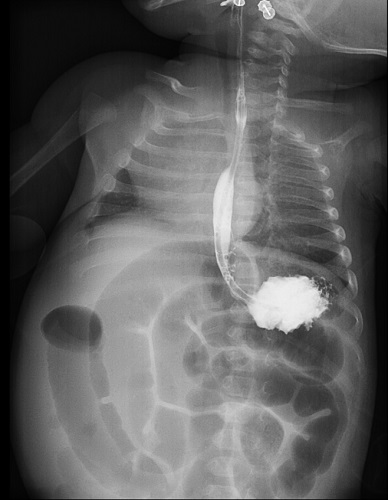

Se realizó tránsito gastrointestinal con leve retención de contraste, pero sin oclusión completa (Figura 1). Ante la falta de progresión se decide exploración quirúrgica, en la que se observa quiste de duplicación intestinal ileocecal que condiciona pseudo-obstrucción. Se realizó resección del quiste, con éxito. El postoperatorio evolucionó favorablemente, con alta hospitalaria tras lograr tolerancia oral completa.

Figura 1. Tránsito gastrointestinal